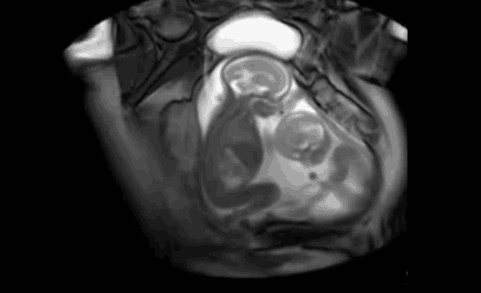

其实,双胞胎有所不同,从医学角度讲,共有三种形式存在。上图这样的属于单绒单羊双胞胎,在妈妈肚子里还是有一定危险性的。

3、单绒单羊双胞胎:有同一个受精卵,两个宝宝共用胎盘且无羊膜间隔。这种是很少见也是风险比较大的。也就是说,两个宝宝在同一个房间生活。他们难免会碰到、脐带绕颈等情况,发生宫内窘迫的可能性增加。

单绒单羊双胞胎风险大

两个宝宝都在一个房间,当然更危险一些,具体表现为,胎儿畸形率、早产、死亡率、生长受限的可能性增加。对母体来说,孕妈患有妊娠合并症的风险指数增加,且两个宝宝可能会因为争夺营养而打架。毕竟,他们是共用胎盘,且胎盘的储存量并不会太多,也增加了脐带绕颈的风险。

尤其是两个宝宝之间没有羊膜阻隔,在孕晚期由于胎儿体积大,活动起来更容易造成脐带绕颈、打结的现象,这样胎儿可能会因为血供中断,导致窒息、死亡。一般医生会建议在32~34周就及时终止妊娠,拖得越久,对孕妈和胎儿越不利。